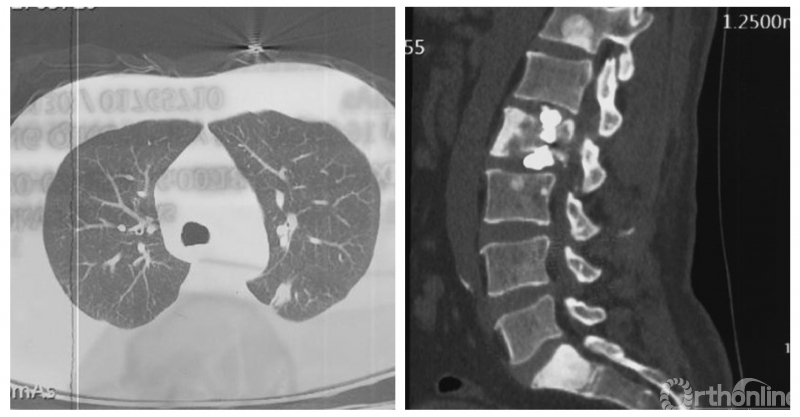

患者房某,男性、51岁。主因“腰痛3个月”入院,既往外院诊断“周围型肺腺癌”,全身检查提示多发骨转移。

经Spine Oncology Study Group(SOSG)评估硬膜外脊髓压迫(ESCC)为Grade 1a型,轻度脊髓压迫;脊柱机械稳定性评估(SINS)7分,中度不稳。修正Tokuhashi评分(RTS)6分,预计生存<6个月,建议姑息性手术及保守治疗;结合Tomita评分系统6分,故行姑息性手术短期控制。

影像学资料

PVP治疗

术后6个月